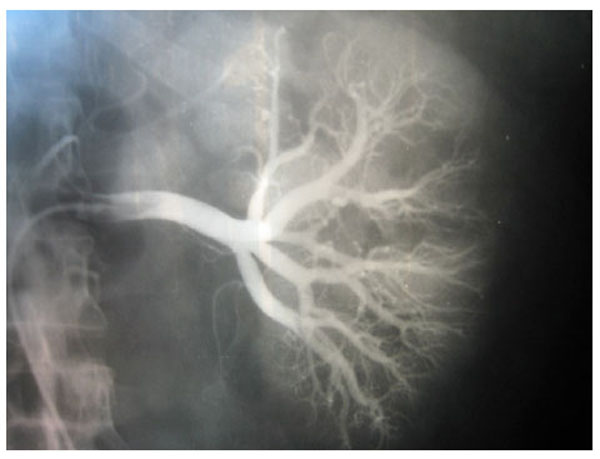

Fig. (3), Fig. (4), Fig. (5), Fig. (6), show images before and after systemic fibrinolytic treatment of two different patients, one suffering from partial emboli occlusion of main renal artery and the other, multiple segmentary intrarenal emboli.

Fig. (3).

Selective arteriography of a right renal artery showing partially emboli occlusion at bifurcation of the main renal artery.